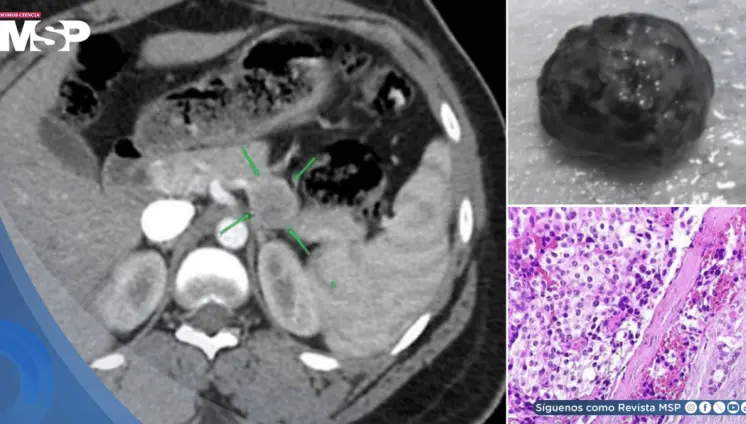

Paciente presenta ruptura intraperitoneal de quiste parasitario después de presión abdominal súbita, manifestando dolor intenso en hipocondrio derecho con irradiación al hombro.